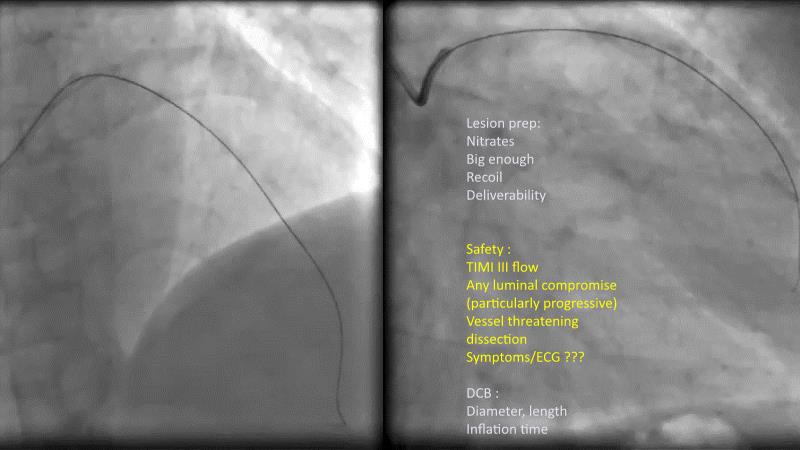

DES and DCB, can these two technologies be complementary for the treatment of the same patient? What are the advantages and how to proceed? You will know everything by watching this presentation based on concrete cases.